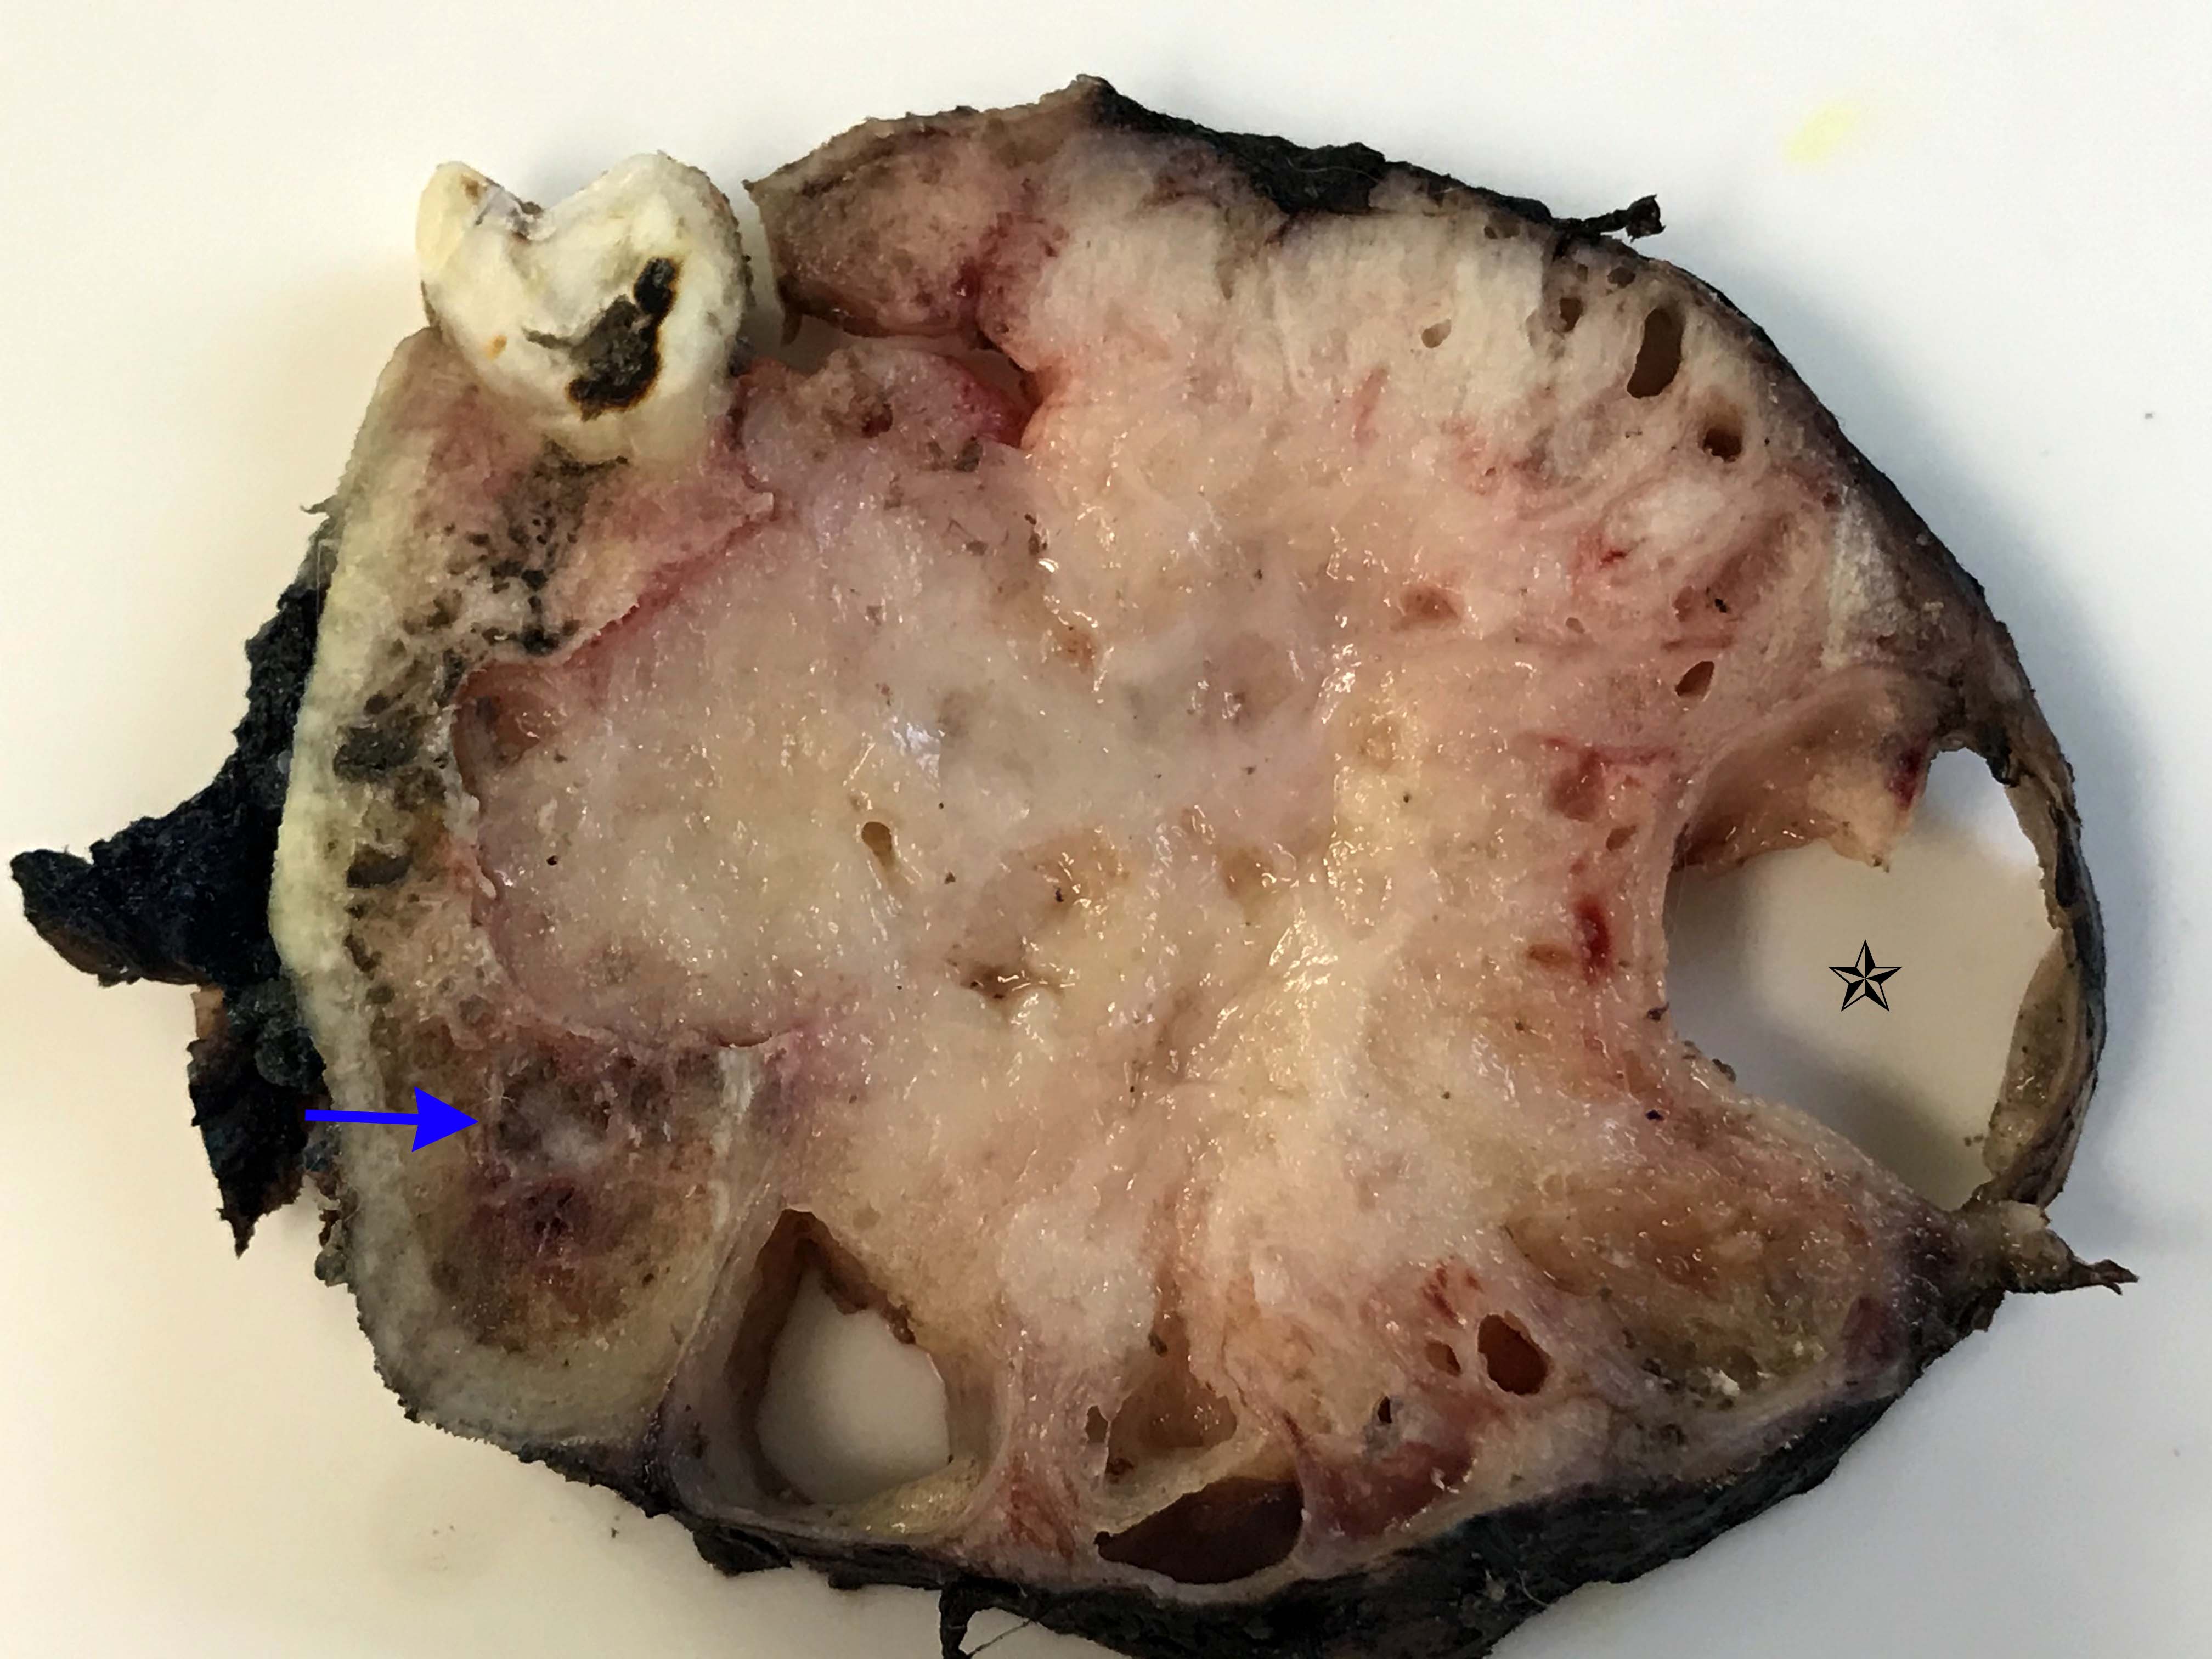

Gross description

- General grossing tips for intraosseous ameloblastoma:

- Prior to sectioning bone, review preoperative radiograph to evaluate for presence and location of any pre-existing metal hardware, titanium dental implants or impacted teeth that could interfere with bone sectioning, could increase difficulty with bone sectioning and be potentially hazardous if unexpectedly encountered

- If possible, recommend submitting at least 1 block as nondecalcified tumor specimen for immunohistochemistry or molecular studies

- Grossly exposed tumor or tumor fragmentation should be documented

- Shaving bone margins for odontogenic neoplasms discouraged:

- Difficulty in measuring extent of tumor from bone margins

- Incidental histologic findings can confound bone margin assessment (Int J Surg Pathol 2020;28:507)

- Ameloblastoma, conventional type:

- Viscous mucoid fluid present on cut surface

- Macrocystic degeneration: larger cystic spaces, may contain clear or red-brown fluid

- Solid, multiple cystic spaces or a combination thereof

- Resorbs tooth roots

- Note expansion or extension beyond bone

- May be associated with impacted tooth

- In mandible, note relation to inferior alveolar nerve if applicable

Gross images